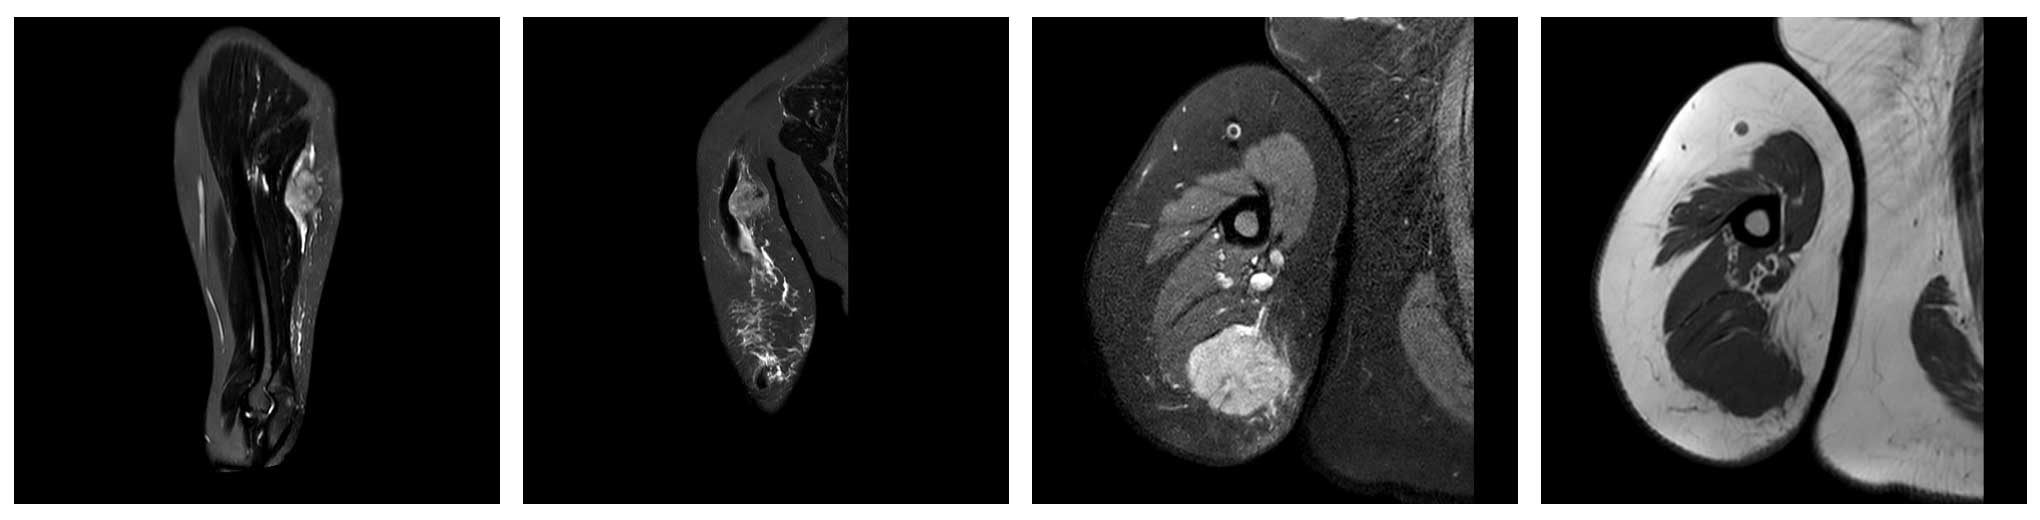

Ameliyat Öncesi: Kol proksimal posterior yerleşimli düzensiz sınırlı heterojen yumuşak doku kitlesi görülmekte.